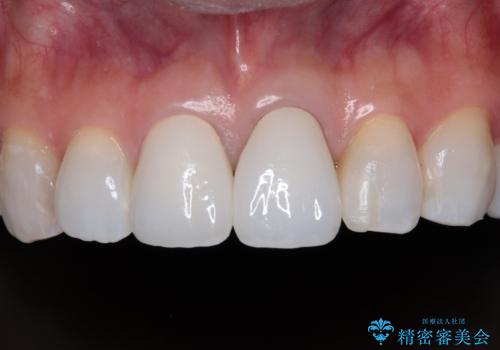

まずは根管治療を行い、症状が消退したことを確認してオールセラミッククラウンにて補綴治療を行うこととしました。

根管治療を行った奥歯は、再発防止や残された歯質を守るため、クラウンによる補綴治療が必要となります。

補綴後6ヶ月経過しレントゲンを撮影したところ、根尖周辺の病変が消失していることが確認できました。